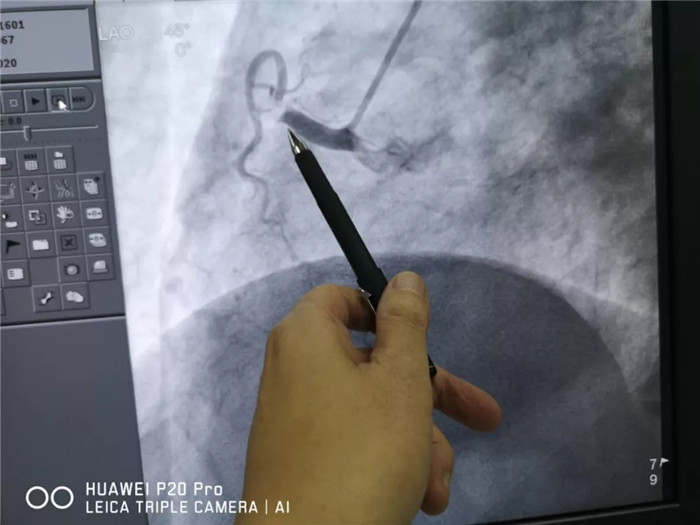

患者生命危急,與家屬溝通同意介入(微創(chuàng))手術(shù);手術(shù)中,患者反復(fù)出現(xiàn)室顫、心臟停止跳動,均搶救成功,手術(shù)順利結(jié)束,患者返回病房。兩天后,患者又出現(xiàn)胸痛、胸悶癥狀,心電圖檢查,支持下壁嚴(yán)重缺血,再行冠狀動脈血管造影復(fù)查,再次血運(yùn)重建手術(shù);目前,患者病情穩(wěn)定,復(fù)查心電圖、心臟B超、CT、化驗(yàn)正常,擬定出院。

西藏阜康醫(yī)院

術(shù)后影像